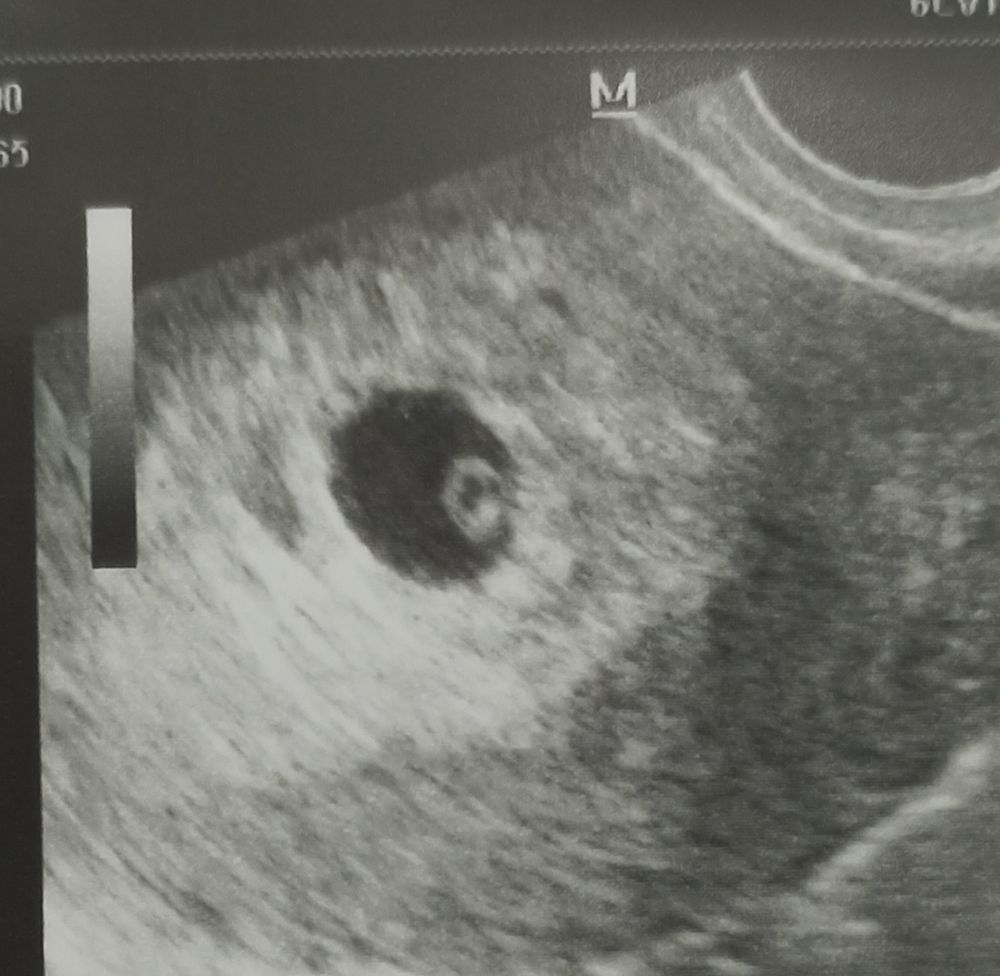

Девочки! Сходила! Слава богу, все хорошо, я лежала как мертвая без эмоций, готовая ко всему, Что-то даже не растрогалась😄 сердечко услышали, яйку с эмби нашли, единственное потеряли ж.мешочек, видимо где-то под ним/за ним, спасибо Вам за поддержку, всех обнимаю 🤗мы будем верить в лучшее, главное теперь до скрининга дотянуть и не поседеть😂

Я сегодня тоже на УЗИ иду) 6+5, но если учесть позднюю овуляцию, то 6+1 наверное. ХГЧ сдавала две недели назад, было 752, сейчас не знаю сколько, но очень надеюсь, что найдут СБ. И вам желаю услышать сегодня сердечко малыша!

Уф! У нас всё хорошо, соответсвуем сроку) и даже сердечко нашли!

Мы тоже нашлись, все хорошо💃💃💃

Удачи Вам, отпишитесь потом! У меня такой же срок)) 7,1, завтра иду на узи, тоже волнуюсь очень!

Кариша, 7+1, но была подтвержденная поздняя О